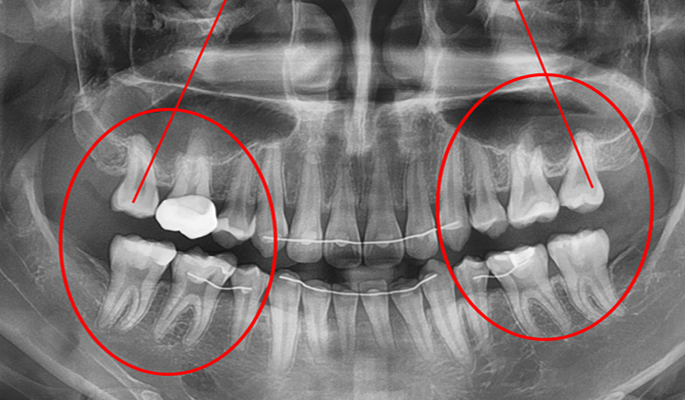

발치 case 2

- 초진

- 왼쪽 위 송곳니가 주변에 치아종이 있어서 더 이상 맹출하지 못한 상태로 내원하심

- 치료 후

- 치아종 및 미맹출 송곳니 발치후 교정치료 및 임플란트 치료 시행함